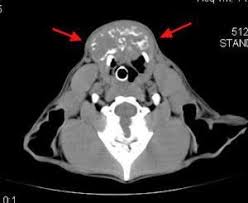

Thyroid Cancer In Dogs Petcure Oncology from petcureoncology.com I am wondering how your dogs did/doing? Cancer research uk said using dogs would be impractical, but discovering the chemicals the dogs can smell could lead to new tests. Sue is most passionate about raising cancer awareness & has developed see something, do aspirate.® to promote early cancer detection and diagnosis. Most service a local area, but some will bring a. Most thyroid gland tumors do not affect thyroid hormone levels. Some people testify by their own experiences that yes, it has been done and it has saved their lives. Dozens of therapy dog organizations across america offer visits. Cancers result from accumulation of mutations over y.

Generally, vets needs to go far beyond blood test results to confirm a cancer diagnosis in a dog or cat. The thyroid is a gland in the neck that produces hormones to regulate metabolism. Sue is most passionate about raising cancer awareness & has developed see something, do aspirate.® to promote early cancer detection and diagnosis. Since i no longer have a thyroid, i have to take hormones that control my metabolism, blood calcium, and energy levels. The lifespan of a dog with malignant cancer is not predictable.

Clinical Rounds Canine Thyroid Carcinoma In 4 Year Old American Bulldog from cdn.sanity.io Since i no longer have a thyroid, i have to take hormones that control my metabolism, blood calcium, and energy levels. We have provided some more information about cancer. Sometimes doctors find neck lumps during a physical exam. Cancer was changing me for the better and showing me how strong i truly am. How long do they keep a dog in the pound before they put him down? If you're wondering, does my dog have cancer? this might be a scary time for you. I'm experiencing this with one of my dogs, a ten year old terrier, right on the heels of losing my other terrier to cancer. Can he really smell cancer even if he isn't trained for it?

Kelsey Thyroid Cancer Survivor Yale Cancer Center from ysm-res.cloudinary.com The lifespan of a dog with malignant cancer is not predictable. Just how can they do it? Can i wash duffel bag in the washing machine. He's got cancer of the spleen, liver and pancreas. Your vet can determine through an examination that the thyroid is enlarged. Whereas we used to expect our pets to die of renal or. I don't have a thyroid anymore. Having cancer was in no way easy, but my life was starting to become more positive because of it.